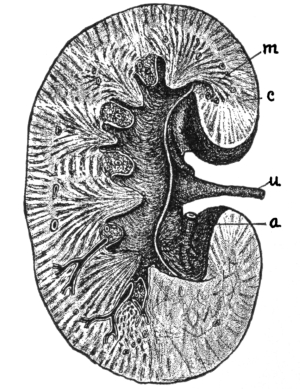

The Abdominal Cavity, 132—Muscles of the Abdomen, 132—The Peritoneum, 134—Abdominal Regions, 134—Salivary Digestion, 136—The Pharynx, 139—The Esophagus, 138—The Stomach, 138—Gastric Digestion, 139—Vomiting, 140—Intestinal Canal, 141—The Small Intestine, 142—Intestinal Digestion, 143—Absorption in Intestine, 144—The Large Intestine, 145—Food and Metabolism, 147—The Liver, 149—The Gall-bladder, 152—The Pancreas, 153—The Spleen, 153—The Suprarenal Capsules, 154—The Kidneys, 155—The Urine, 156—The Ureters, 159—The Bladder and Urethra, 159. |